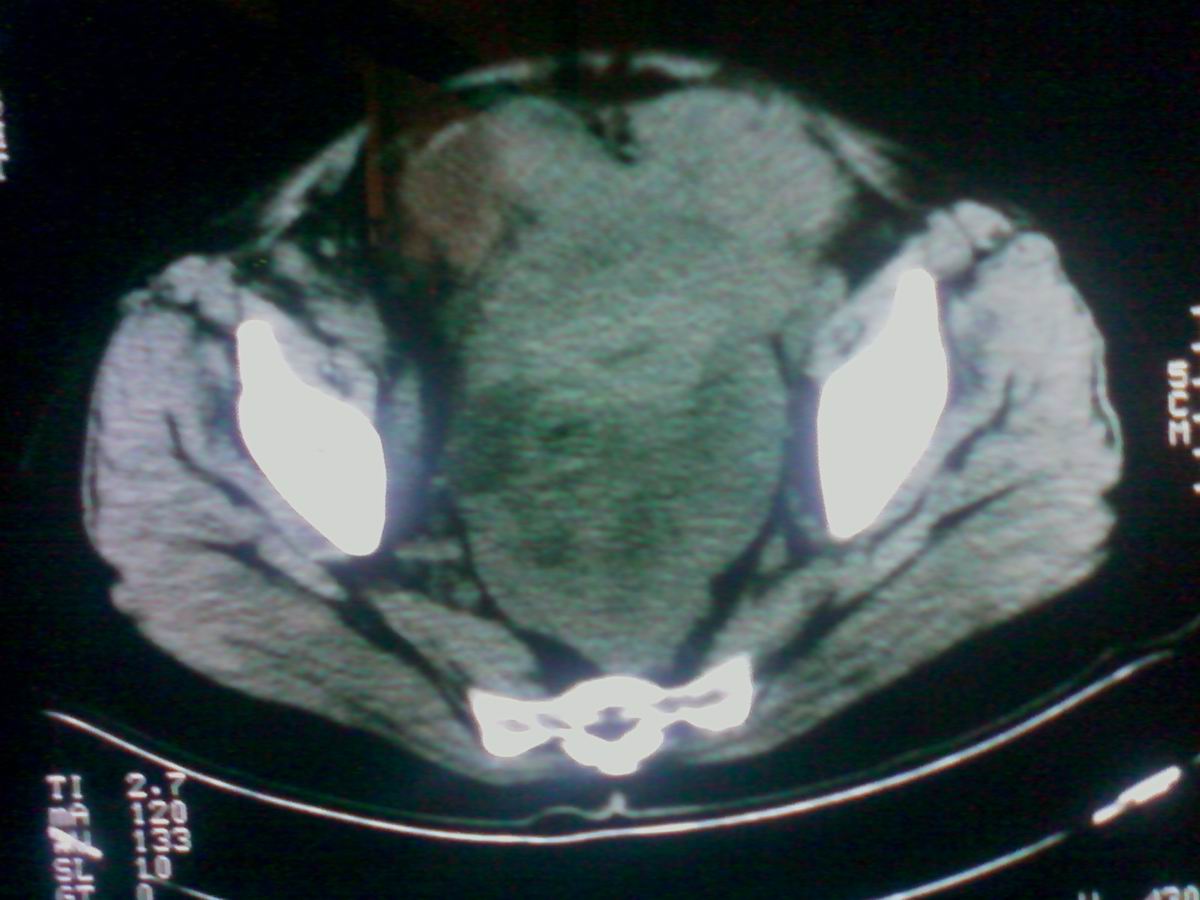

标题: CT25799:女性患者,45岁,腹胀,上腹部疼痛来诊,B超示盆腔 [打印本页]

标题: CT25799:女性患者,45岁,腹胀,上腹部疼痛来诊,B超示盆腔

考虑卵巢癌伴腹水

1)考虑卵巢恶性肿瘤。2)腹水。